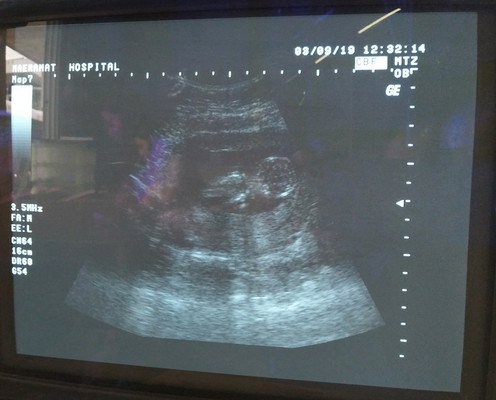

15Wแล้วค่ะตอนนี้สอบถามแม่ๆๆว่าถ้าไปซาวตอนนี้จะเห็ณเพศน้องมั้ยค่ะ

ปล....ภาพนี้ซาวตอน13Wค่ะแม่ๆๆถ่านไหนดูออกบ้างค่ะ

เพศจะเห็นชัดตอน 16W ขึ้นไปจ้า แต่ 15 นี่ก็น่าจะเห็นค่ะแต่ไม่น่าชัด